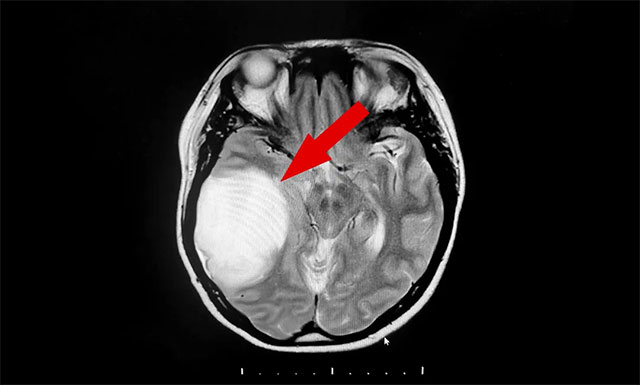

由于当地医疗条件所限,患者遂在亲友推荐下慕名来到上海蓝十字脑科医院寻求进一步诊断治疗。入院后,经头颅增强核磁检查,发现患者右侧颞叶单发巨大混杂信号占位病变,病灶约 5.4×6.7×4.9 cm,结合病灶影像特点,诊断其为胶质瘤可能性较大。

▲ 患者右侧颞叶单发巨大混杂信号占位病变